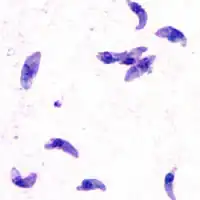

| Toxoplasma gondii tachyzoites | |

The Eucoccidiorida are an order of microscopic, spore-forming, single-celled parasites belonging to the apicomplexan class Conoidasida. Protozoans of this order include parasites of humans, and both domesticated and wild animals including birds. Among these parasites are the Toxoplasma gondii that cause toxoplasmosis and Isospora belli, which results in isosporiasis.